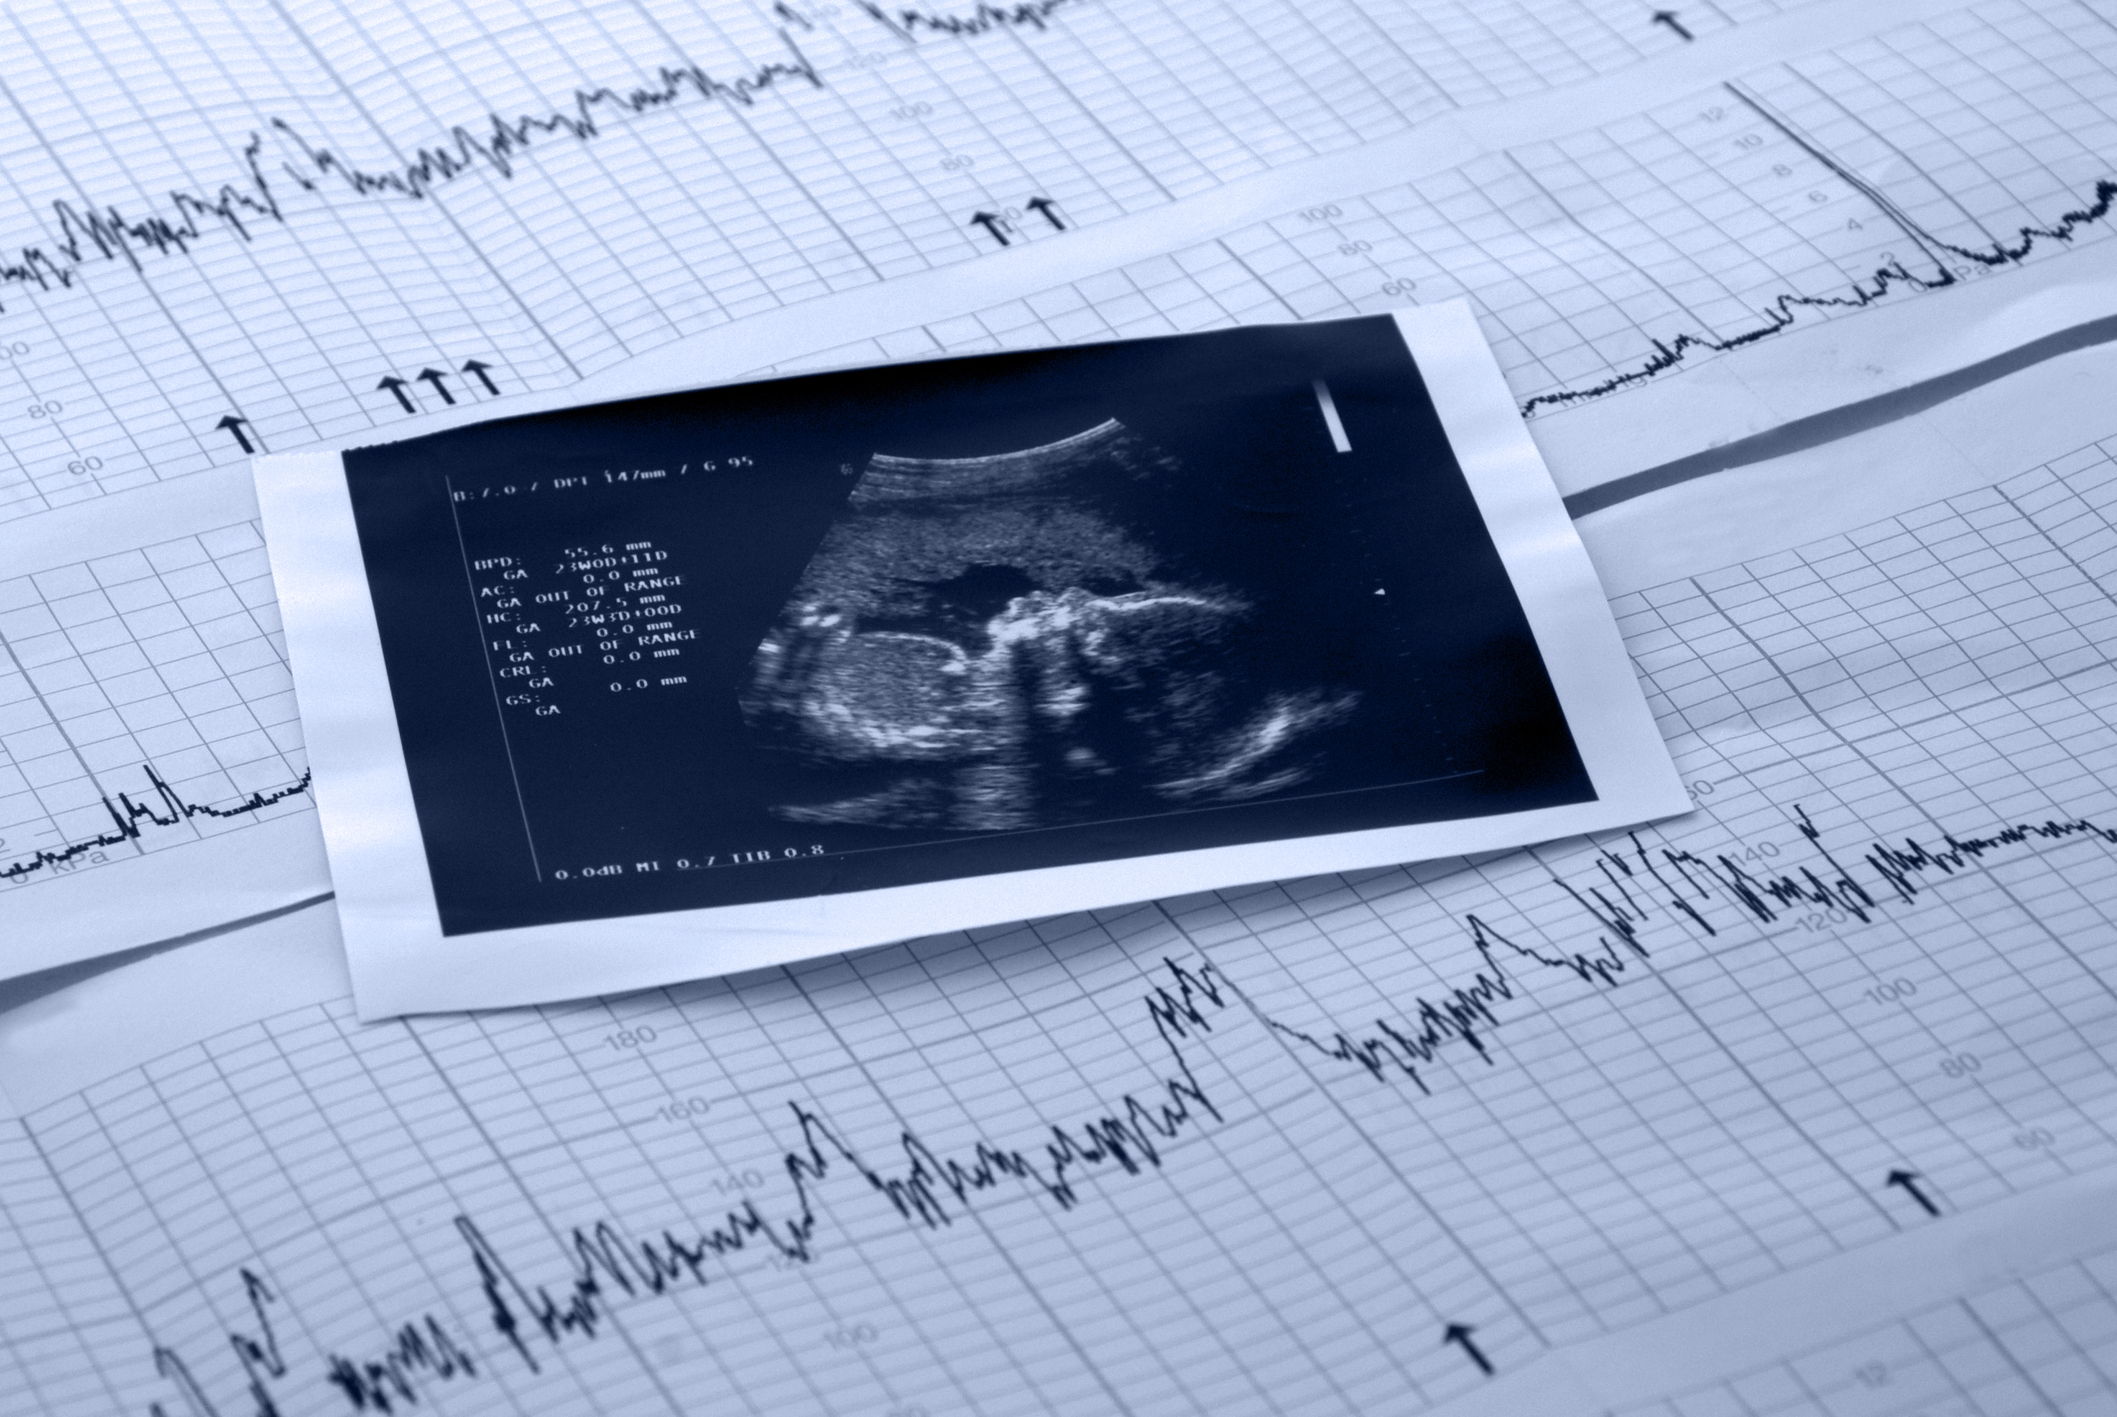

A vacuum extraction delivery is a medical procedure performed during vaginal childbirth. It is a type of assisted delivery wherein the doctor places a vacuum extractor or a soft, cup-shaped device on your baby’s head. The baby is gently and safely suctioned down the birth canal while the mother pushes.